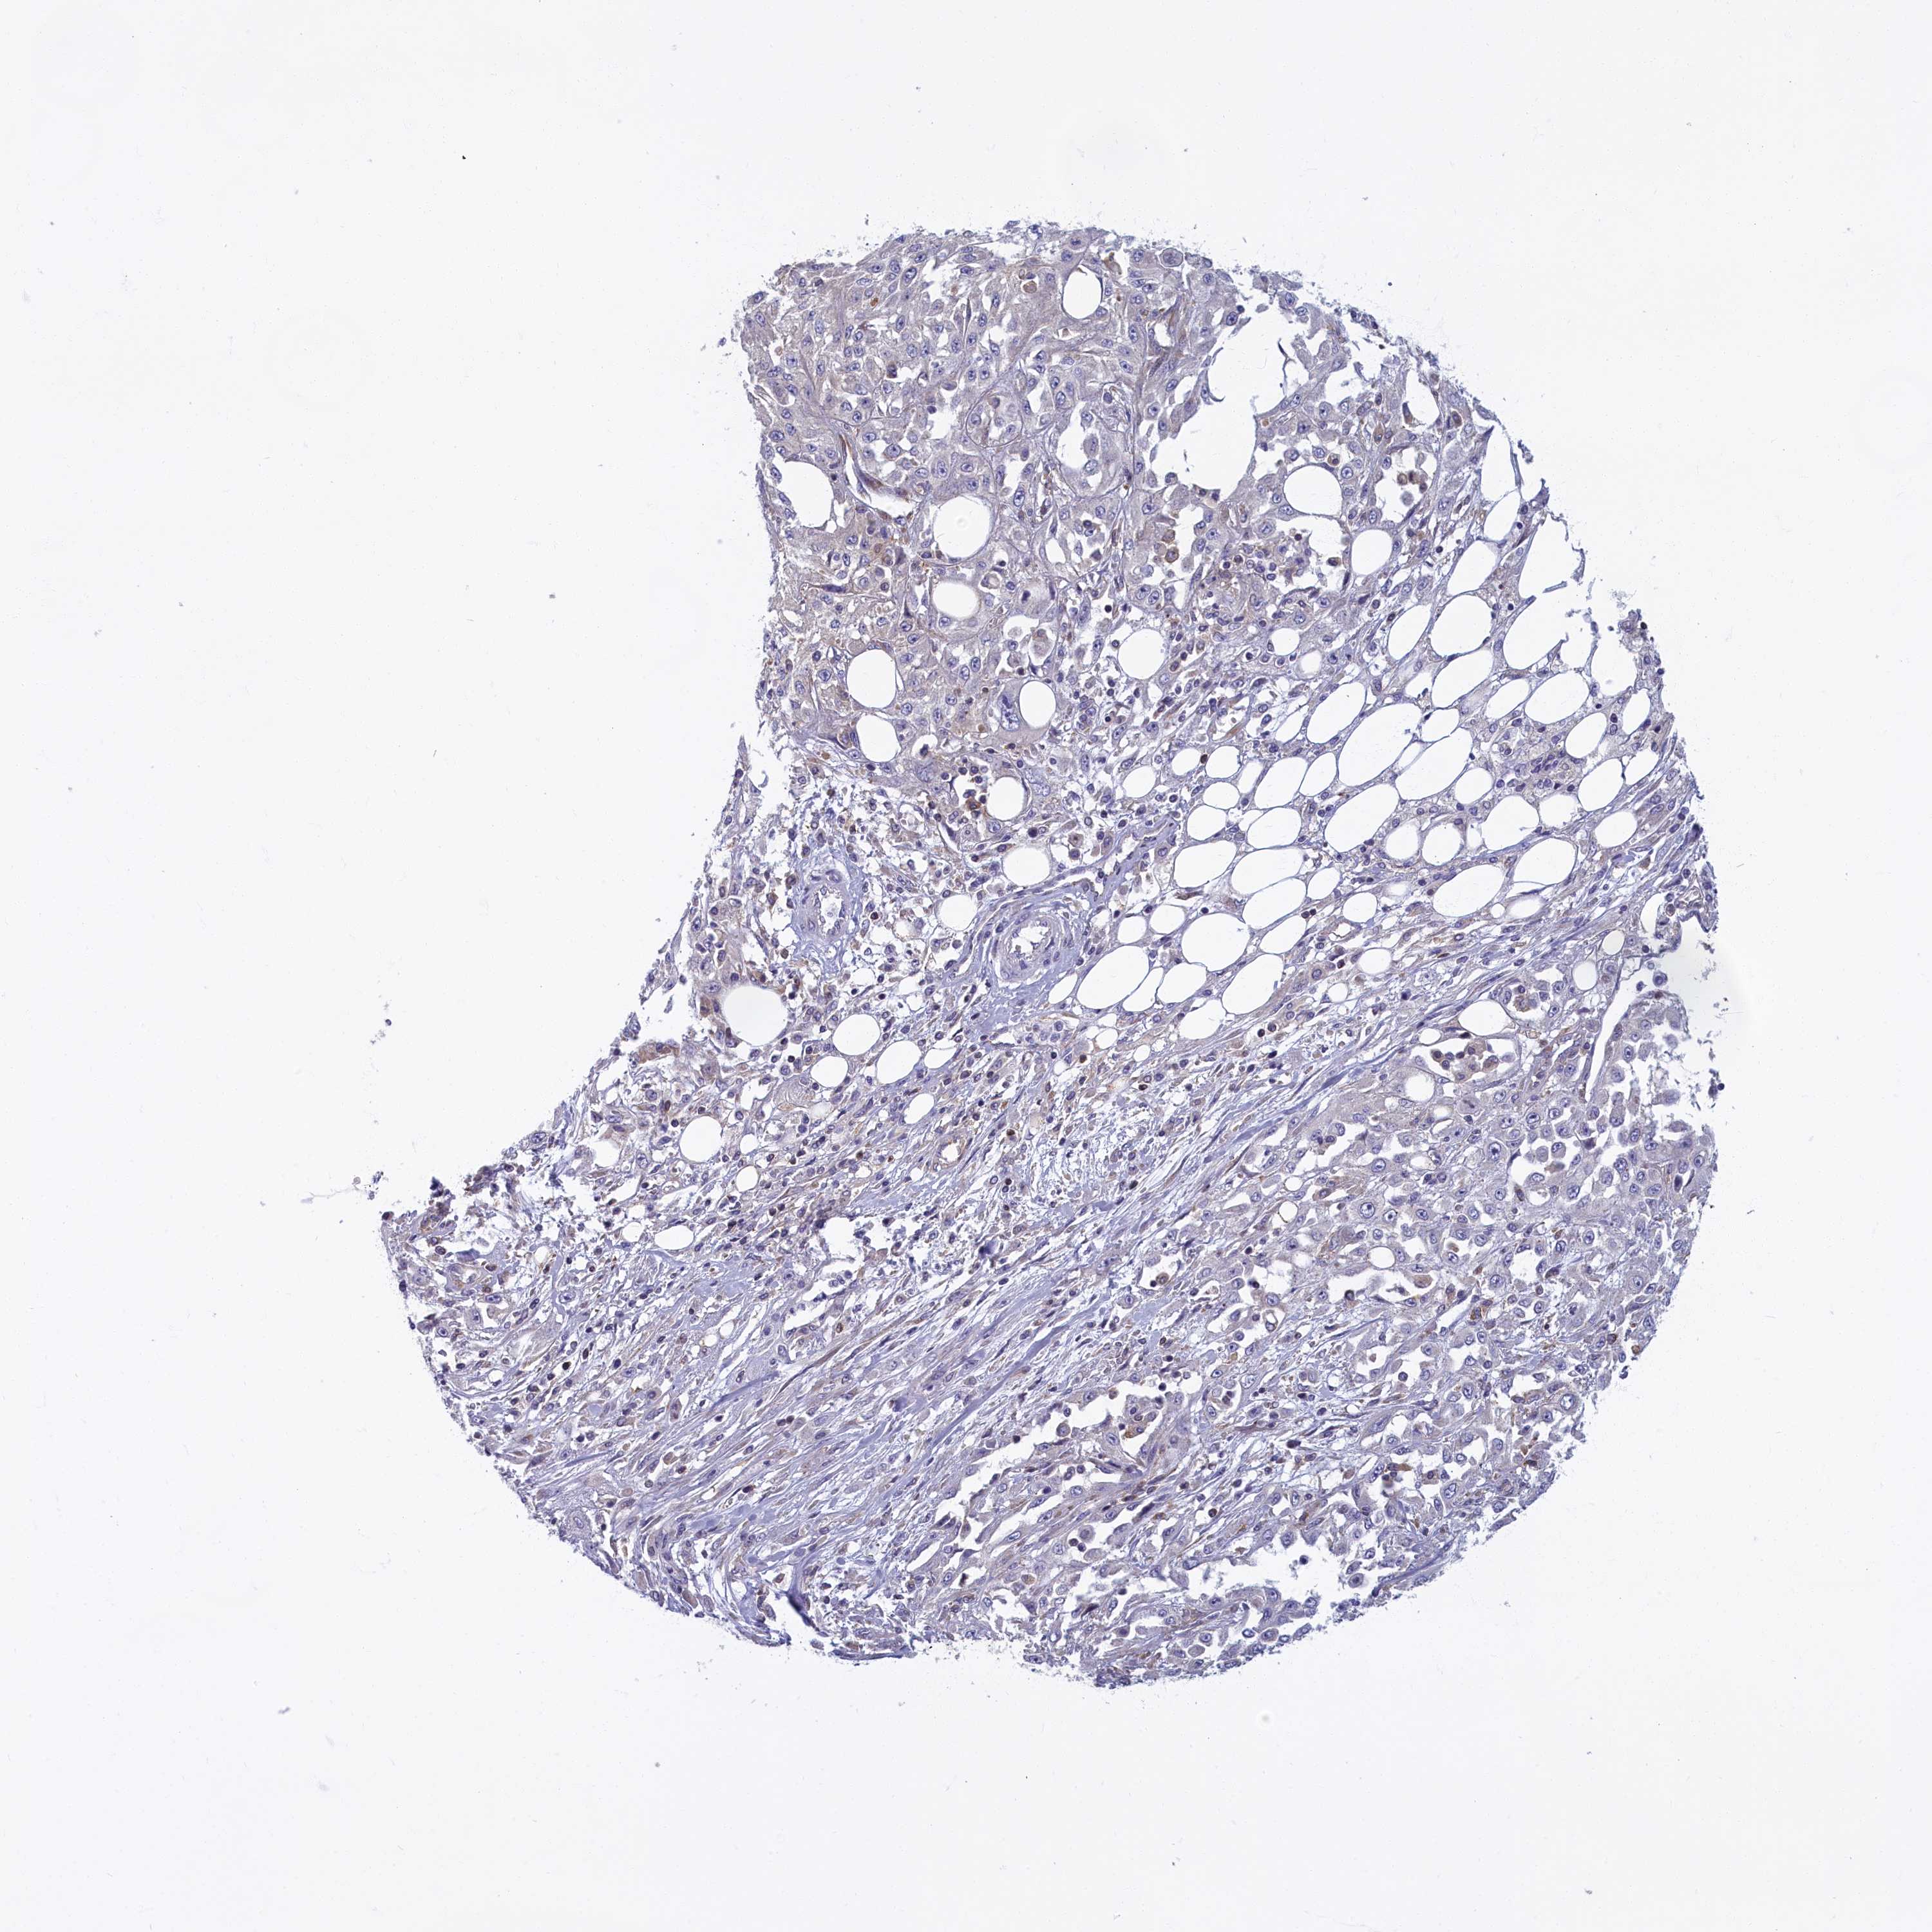

CANCER SKIN CANCER Show tissue menu

Basal cell and squamous cell cancer

SKIN CANCER - Protein expressioni

A mouse-over function shows sample information and annotation data. Click on an image to view it in a full screen mode. Samples can be filtered based on level of antibody staining by selecting one or several of the following categories: high, medium, low and not detected. The assay and annotation is described here.

Each image is clickable and will lead to virtual microscopy that enables deeper exploration of all samples and also displays staining intensity scores, fraction scores and subcellular localization as well as patient and tissue information for each sample.

Antibody HPA043075

Staining

High

Medium

Low

Not detected

Intensity

Strong

Moderate

Weak

Negative

Quantity

>75%

75%-25%

<25%

None

Location

Nuclear

Cytoplasmic/membranous

Cytoplasmic/membranous,nuclear

Basal cell carcinoma

Squamous cell carcinoma, NOS

Squamous cell carcinoma, metastatic, NOS